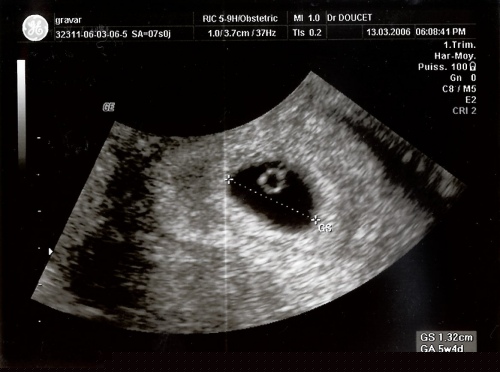

13 mars 2006 - Echographie

Le 13 mars 2006, on me prend en photo pour la première fois. Je ne ressemble pas encore à grand chose, il faut bien le reconnaître.

Mais bon, ce docteur avait raison, Maman a bien un sac dans le ventre.